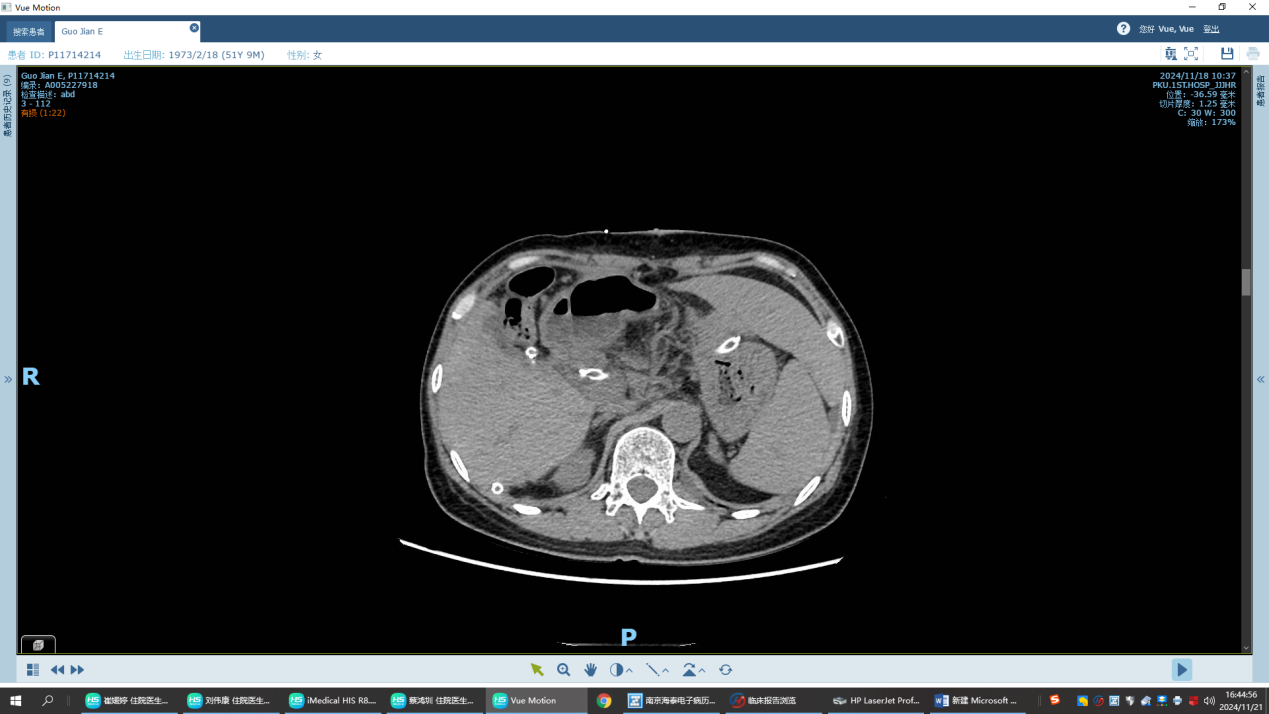

经过短短暂的ICU监护,患者术后很快转回了普通病房。术后5天,患者的血小板由16*109/L升至81*109/L,术后9天升至129*109/L,已达正常范围。相比术前,目前患者的纤维蛋白原已恢复正常,D-二聚体和纤维蛋白降解产物也稳步下降。

术后8天复查CT